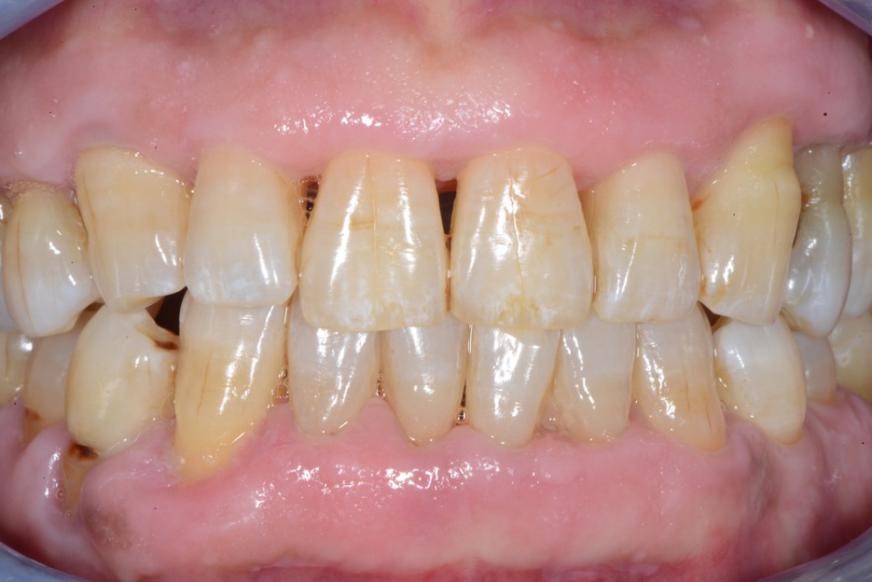

图4:牙周基础治疗后

图3:牙周炎治疗前